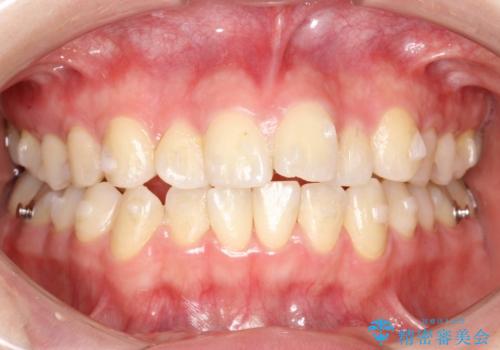

インビザラインによるガタつきの矯正治療 シンプル・短期間

- 20代女性

- invisalign full

- 1年6ヶ月

- 非抜歯、IPR+拡大によるマウスピース矯正を計画した。

一見前歯のガタつきだけのように見えても、そのガタつきの根本的な原因が奥歯の位置であったりすると、マウスピースの枚数がそれなりに多くなり、治療に時間がかかることもあります。